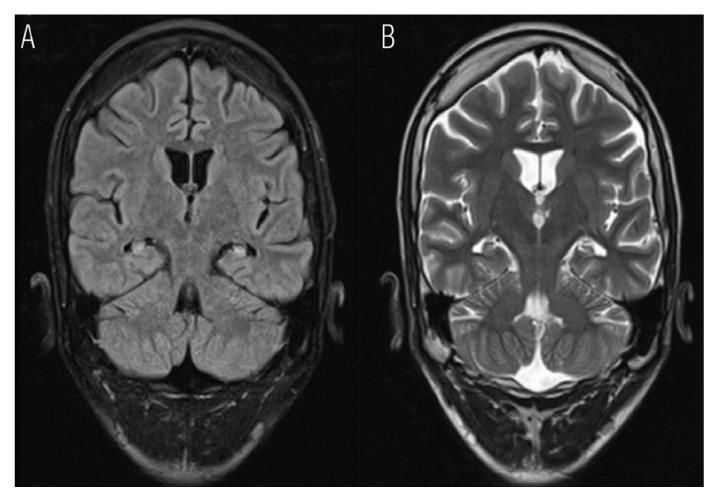

奥曼患者双侧颞叶内侧硬化症发作间期饮水

Peri-ictal Water Drinking in an Omani Patient with Bilateral Mesial Temporal Sclerosis.

Peri-ictal water drinking (PIWD) is a rare vegetative manifestation of temporal lobe epilepsy without a definite lateralisation value. We report a case of PIWD in a 22-year-old Omani male patient with post-concussion syndrome and epilepsy presented to a tertiary care hospital in Muscat, Oman, in 2021 for evaluation of paroxysmal events. His behaviour of PIWD was misinterpreted by his family until characterised in the epilepsy-monitoring unit as a manifestation of epilepsy that was treated medically. To the best of the authors' knowledge, this is the second reported case in the region.

摘要

发作间期饮水(PIWD)是一种罕见的无明确侧化价值的颞叶癫痫的植物状态表现。我们报告了 2021 年在阿曼马斯喀特的一家三级护理医院就诊的 1 例有脑震荡后综合征和癫痫的 22 岁阿曼男性患者的 PIWD 病例,以评估阵发性事件。他的发作间期饮水行为被家人误解,直到在癫痫监测单元被确定为癫痫的一种表现形式,并接受了药物治疗。据作者所知,这是该地区的第二例报告病例。